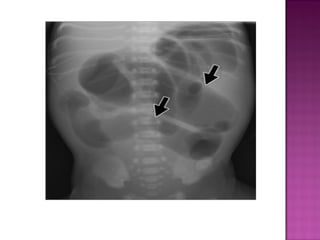

 On AXR gas filled distended stomach &

duodenal cap.

 Absent distal bowel gases,

 Congenital failureof recanalization.  Association with VATER/VACTERL & trisomy 21.  Post-ampullary.  Bilous vomitting.

• 12.

 On AXRgas filled distended stomach & duodenal cap.  Absent distal bowel gases,